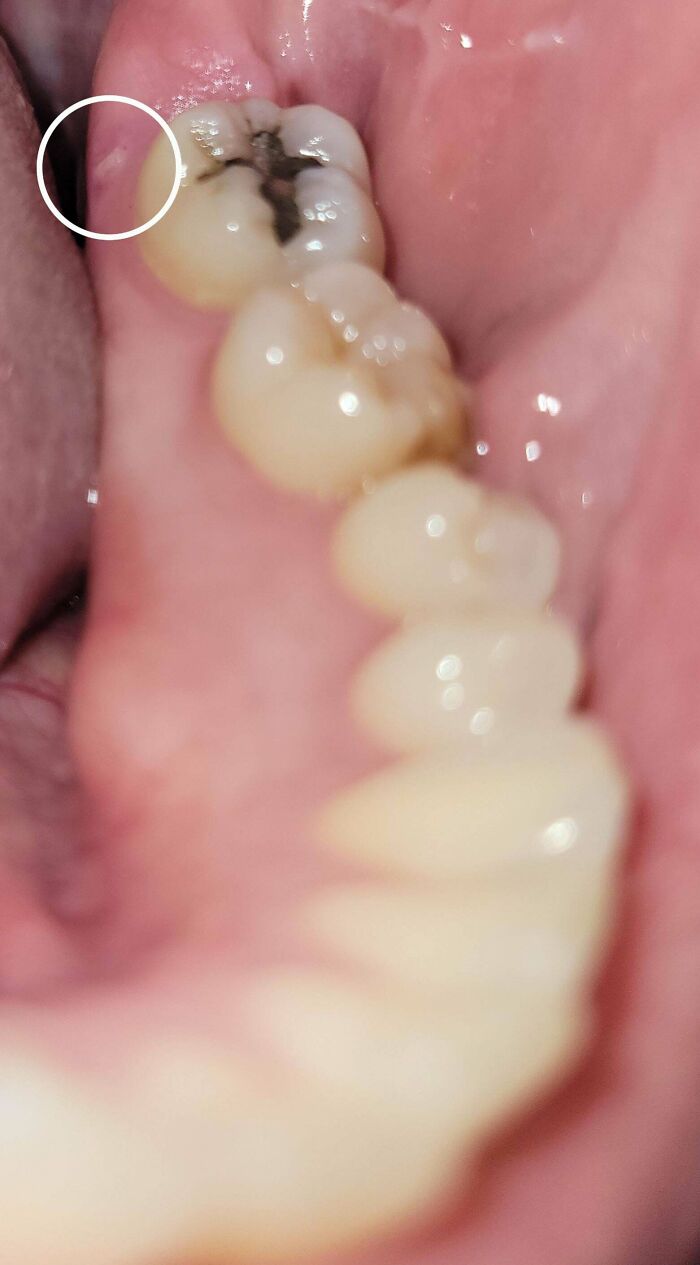

#24 Small Shard Of Bone Emerged 14 Years Post Wisdom Tooth Extraction

Image source: 5ummerbreeze